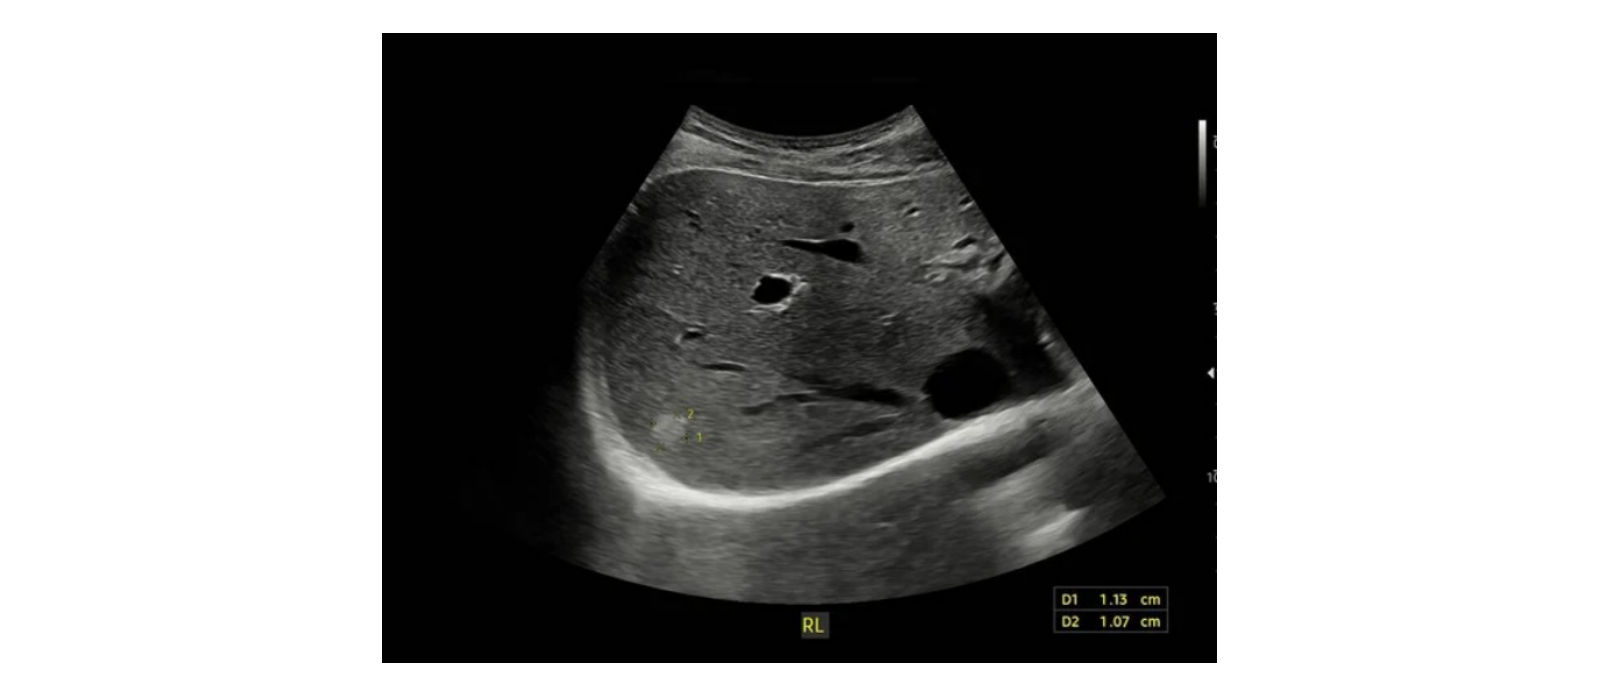

De Transjugulaire Intrahepatische Portosystemische Shunt (TIPS) is een belangrijke interventie bij portale hypertensie. Echografie speelt een centrale rol bij de follow-up en het vroegtijdig opsporen van shuntdisfunctie. Deze presentatie behandelt de anatomie, hemodynamiek en echografische kenmerken van een TIPS, inclusief Dopplerparameters en veelvoorkomende complicaties, zodat deelnemers shuntonderzoek in de klinische praktijk effectief kunnen uitvoeren en interpreteren.